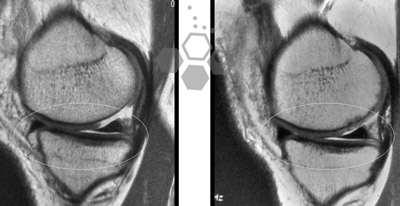

Stem Cells for Treating Meniscus Tears

Stem Cell therapy for meniscus tears is the most common type of knee injury we treat. Surgically repairing a meniscus tear should be considered the last option. Meniscus tear repairs work by surgically removing some (partial meniscectomy), or all of a critical structure in the knee. For most cases, we see, a minimally invasive combination of stem cells, PRP, and post-therapy physical rehabilitation is usually a safer and better option. [3]

The meniscus is a crescent-shaped fibrocartilaginous structure that acts as both spacers between the femur and tibia while also providing shock absorption capabilities for the knee joint. It can be an effective shock absorber by equally distributing any blunt forces across the knee joints. A meniscus is composed of living fibrocartilage tissue, and each knee has two menisci.

Knee Meniscus Tears & Cartilage Loss

The medial meniscus is usually the most injured part of a knee. Most acute traumatic meniscus tears we treat happen due to sudden and traumatic twisting of the knees. For some elderly patients, traumatic injuries and meniscus tears are caused over the gradual weakening of the meniscus as a result of degenerative or arthritic joints. Meniscus tears are usually described by the position/location of the damage (posterior or anterior) and which one of the two menisci that were injured (lateral or medial) Some examples for meniscus tears include: